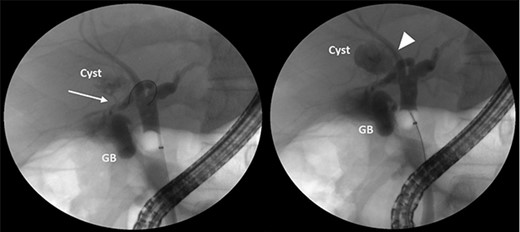

A 35-year-old man presented with a history of recurrent episodes of epigastric pain. Ultrasonography revealed an intrahepatic cyst (Fig. 1), and magnetic resonance cholangiography revealed that the cyst was connected to the cystic duct and right anterior sectoral bile duct (Fig. 2). The patient underwent an endoscopic retrograde cholangiography, which showed that the contrast could fill the cyst (Fig. 3). The laboratory findings, including a complete blood count, showed a white blood cell count of 4200/mm3 (lymphocyte 23%, neutrophil 62%); haemoglobin level of 16 g/dL; platelet count of 215 × 103/ mm3; total protein of 7.8 g/dL; albumin of 4.3 g/dL; total bilirubin level of 0.68 mg/dL; serum aspartate aminotransferase level of 26 IU/L; serum alanine aminotransferase level of 29 IU/L and alkaline phosphatase level of 105 IU/L. Tumour markers, including alpha-fetoprotein, carcinoembryonic antigen and carbohydrate antigen 19–9 were within normal limits. Viral markers for hepatitis B and C were negative. Due to the preoperative diagnosis of a type VI choledochal cyst, with a differential diagnosis of cystic intraductal papillary neoplasm of the bile duct, the patient underwent laparoscopic right anterior sectorectomy to excise the cyst completely. During the operation, after identifying the cystic duct and taking down the fundus and body of the gallbladder from the liver bed, an intraoperative cholangiogram was performed via the cystic duct connected to the cyst. Right anterior sectorectomy was then performed (Fig. 4). The postoperative period was unremarkable, and the patient was discharged on the sixth postoperative day. Pathological examination revealed a cyst with a fibrous wall, dense chronic inflammatory infiltration, lined by columnar epithelium. Mild reactive atypia, associated with marked chronic inflammatory cell infiltration, was noted. No signs of epithelial dysplasia were observed (Fig. 5).

Pathological examination revealed a cyst with a fibrous wall (arrow), dense chronic inflammatory infiltration, lined by columnar epithelium (arrowhead). Mild reactive atypia, associated with marked chronic inflammatory cell infiltration, was noted. No signs of epithelial dysplasia were observed.